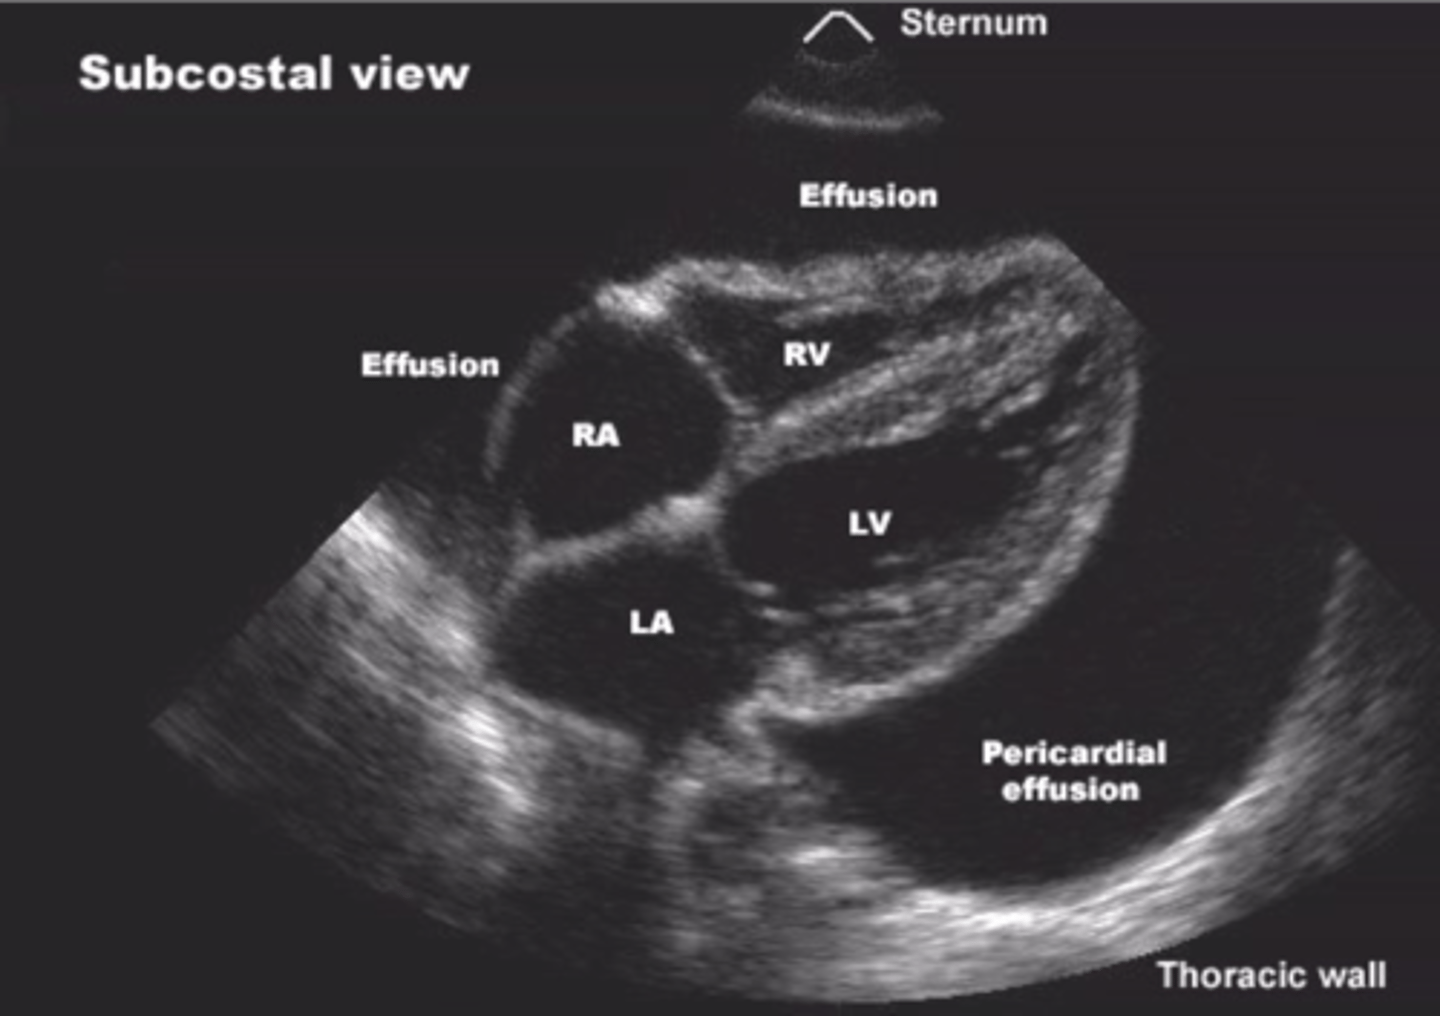

Pericardium

sac made up of a double membrane, encloses the heart